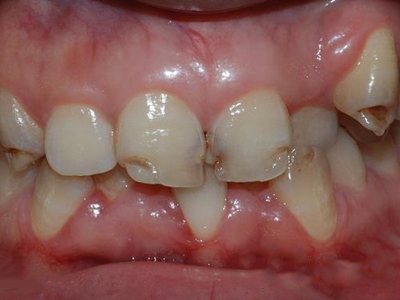

牙釉质发育不全牙齿棕色有缺损图

牙釉质发育不全患者牙齿出现明显的缺损表现,并于表面形成深褐色的蜂窝状、竖条状的凹坑,甚至形成洞,患者上下牙失去咬合能力。